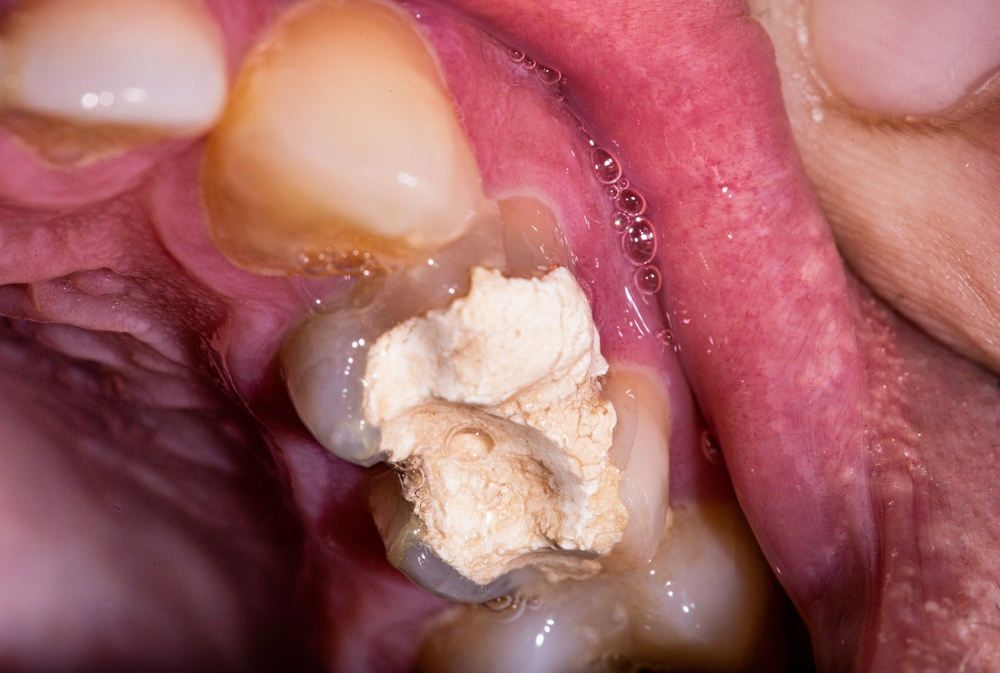

There are so many elements that you need to consider when it comes to improving your oral health, and something like getting a tooth filling is one of the best and most effective ways in which you can achieve this. However, you also need to understand some of the best ways of being able to deal with this more effectively when it comes to taking care of your teeth better.

It is important to make sure you come up with some of the best ways of being able to look after your teeth better, and this means focusing on the things you need to avoid after a tooth filling. In this blog post, we are going to explore the different reasons you might need a tooth filling, what you should avoid after getting one, and how Eye & Dental Clinic can help you.

A tooth filling is one of the most important ways of being able to improve your oral health and hygiene, and this is something that might be required at some point in helping you achieve this. There are some of the best ways of being able to treat tooth problems, and it can be essential to do this before the situation becomes worse. There are a lot of problems with your teeth that you might encounter over the years, and if things become bad, you might need to get professional work done to protect your oral health long-term. This is something you need to get sorted, and a tooth filling is a key part of this.

Many dental treatments are essential for guarding against damage or infection, and others are perfect for boosting cosmetic and aesthetic purposes. Getting a tooth filling, even a temporary tooth filling, is something that you can help to fulfil both of these elements, and this is why it is so important to try to make the right changes that are going to help you make the right improvements here. Getting a tooth filling can be a major part of dental healthcare, and this is something you need to consider if you want to boost your teeth and gums.

There are plenty of things that you need to think about when it comes to making your mouth better, and this is something that plays a big role in helping you make the most of this. It is vital to ensure that you are going to take the right steps that will help you make your teeth and gums stronger and healthier, and this is something that you have to make the most of. Getting a tooth filling is one of the key ways of staying on top of oral health and hygiene, and you need to know how long after your filling you can eat.